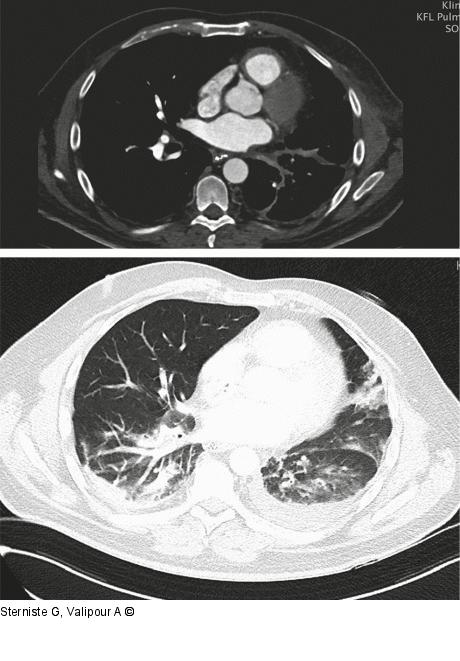

Abbildung 4: Computertomographie

Computertomographie April 2022